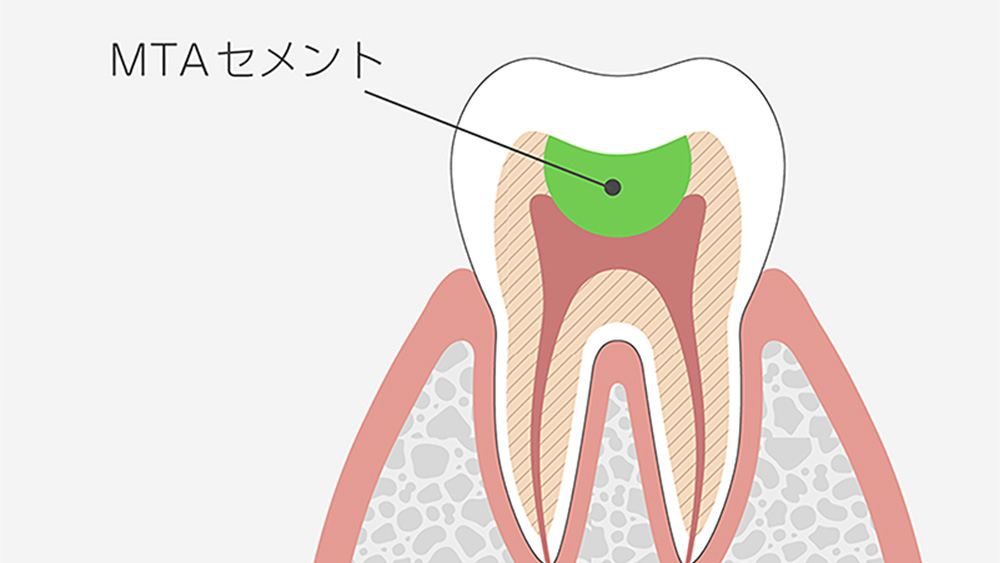

当院では、しなやかで歯に優しいファイバーコアや、優れた生体親和性を持つMTAセメントなどを用いて、残っている歯の構造を最大限に活かしながら、被せ物を安定させるための土台作りを行っています。